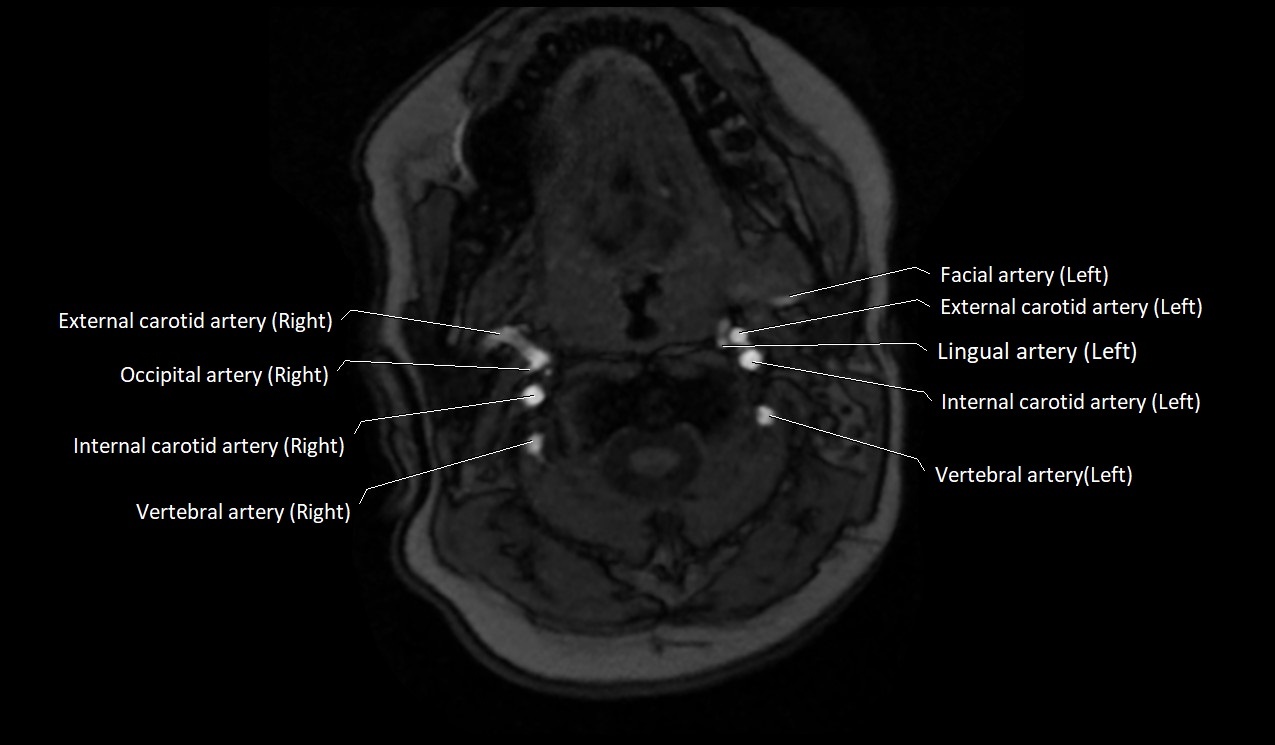

MRI images

image